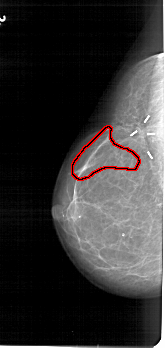

FILE: A_1613_1.LEFT_CC.OVERLAY

TOTAL_ABNORMALITIES 1

ABNORMALITY 1

LESION_TYPE CALCIFICATION TYPE PLEOMORPHIC DISTRIBUTION LINEAR

ASSESSMENT 5

SUBTLETY 4

PATHOLOGY MALIGNANT

TOTAL_OUTLINES 1

BOUNDARY